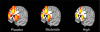

Methods: This study examined the impact of a placebo [breath alcohol concentration (BrAC) = 0.00%], moderate (BrAC = 0.05%), and high (BrAC = 0.10%) doses of alcohol on brain hemodynamic activity during a functional MRI (fMRI) Go/No-Go task in 38 healthy volunteers.

Results: Alcohol increased reaction time and false alarm errors in a dose-dependent manner. fMRI analyses showed alcohol decreased activity in anterior cingulate, lateral prefrontal cortex, insula, and parietal lobe regions during false alarm responses to No-Go stimuli.

Conclusions: These findings indicate that brain regions implicated in error processing are affected by alcohol and might provide a neural basis for alcohol's effects on behavioral performance.